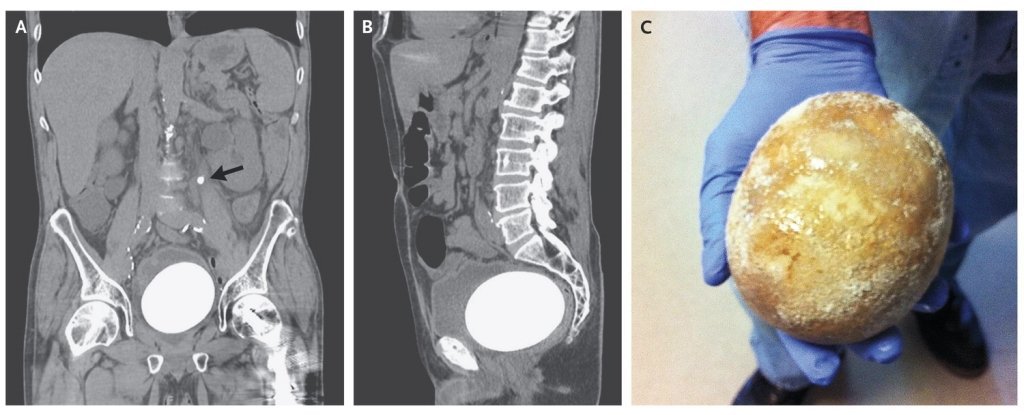

Tomografiile computerizate au dovedit existenţa a două pietre în vezica urinară a bărbatului. Piatra cu dimensiuni reduse a fost descoperită în uretra ce conectează rinichiul stâng de vezică, iar a doua piatră cu o dimensiune gigantă a fost descoperită în vezică.

Piatra are o mărime de 12 pe 9,5 centimetri şi cântăreşte 770 de grame. Pietrele din vezică sunt generate de inflamarea organului. Această afecţiune are loc atunci când organismul este deshidratat sau urina este prea concentrată, astfel în vezică se formează cristale care în timp produc apariţia pietrelor.

Desigur, majoritatea oamenilor nu dezvoltă pietre atât de masive, cazul de faţă fiind unul special. Timp de 10 ani, bărbatul a suferit de o formă de cancer agresivă în urma căreia vezica i-a fost îndepărtată şi reconstruită cu ajutorul unei bucăţi din intestin. Acest tip de vezică este deseori susceptibilă la formarea pietrelor. În timp, medicii au descoperit că boala poate debuta fără apariţia simptomelor, astfel poate ajunge la dimensiuni impresionante.